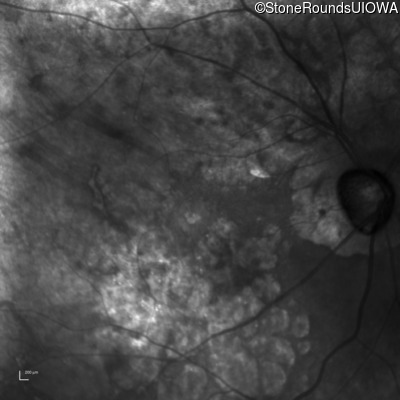

This 81 year old man began using a flashlight to read menus in his 40's. At age 75 his ophthalmologist noticed abnormal fundus findings and referred him to a retina specialist.

Diagnosis & molecular findings

| Late Onset Retinal Dystrophy | C1QTNF5 | Ser163Arg AGC>AGA | AD |

Disease:

Gene:

Allele 1:

Ser163Arg AGC>AGA

Inheritance:

AD